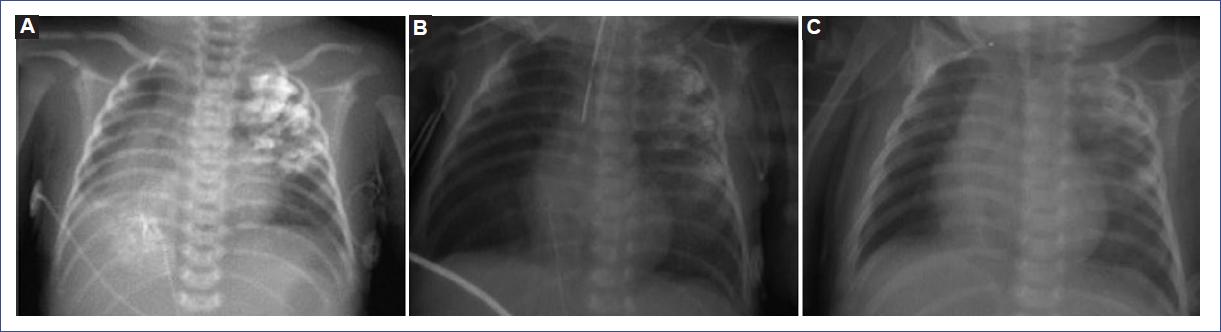

Se realizó radiografía de tórax que mostró una radioopacidad heterogénea, densidad metal, en la región apical izquierda, de bordes mal delimitados, con tendencia a confluir; en el hemitórax derecho, radioopacidad heterogénea, densidad metal en la región basal interna y radioopacidad homogénea hiliar con signo de la silueta (Fig. 1A).

Figura 1 A: radiografía inicial, previa al lavado broncoalveolar. B: control radiográfico posterior al primer lavado broncoalveolar. C: radiografía de control en consulta externa, 1 mes posterior al egreso.

Se realizaron broncoscopia con equipo flexible de 3.8 mm y LBA, identificando una hipersecreción blanquecina abundante, con salida de filamentos blanquecinos, espesos a la aspiración, administrando alícuotas de 5 ml de solución salina tibia, en total 80 ml. No se observó fístula traqueoesofágica. Sin complicaciones. La radiografía de control mostró desaparición de la radioopacidad basal derecha y disminución de la imagen apical izquierda (Fig. 1B), por lo que se decidió realizar nuevamente el procedimiento 3 días después, con LBA y alícuotas de 5 ml en seis ocasiones, orientadas a bronquio para el lóbulo superior izquierdo. Al presentarse un episodio de desaturación reversible, se interrumpió el procedimiento. Se reportó traqueobronquitis membranosa moderada, con aislamiento en cultivo de Pseudomonas aeruginosa. Se programó para una tercera broncoscopia 1 semana después, en la que se realizó LBA con alícuotas de 5 ml, en total 50 ml, orientado al lóbulo superior izquierdo, finalizando el procedimiento sin complicaciones. Durante su hospitalización se le administró antibiótico, por sospecha de sepsis, y esteroide parenteral. Se realizó gastrostomía como manejo de la atresia esofágica.

Fue egresada posterior a los procedimientos y evaluada 1 mes posterior, con estabilidad respiratoria y mejoría en la imagen radiológica (Fig. 1C). Continúa en seguimiento en consulta.